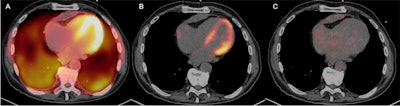

Having patients with cardiac sarcoidosis follow a ketogenic diet for three days before their PET/CT scans can improve image quality by suppressing signal from normal myocardial activity, according to a March 26 study in the Journal of Nuclear Medicine.

Researchers from the University of Minnesota compared more than five years of data on the effects of three different dietary modifications prior to FDG-PET/CT scans in patients suspected of cardiac sarcoidosis. They found that a 72-hour daytime ketogenic diet resulted in increased myocardium suppression and diagnosis rates.

Cardiac sarcoidosis is a rare disease characterized by the formulation of granulomas in the tissue of the heart, and it can cause arrhythmias and heart failure. FDG-PET/CT has emerged as a promising alternative to invasive biopsies for diagnosing the condition, yet for physicians to be able to differentiate between normal physiologic myocardial activity and abnormal myocardial inflammation, the patient's consumption of glucose needs to be suppressed.

- Diet A, a 24-hour ketogenic diet with overnight fasting (n = 94)

- Diet C, a 72-hour ketogenic diet with overnight fasting (n = 98)

"We identified superior myocardial suppression with the 72-hour preparation indicated by a higher blood pool/myocardium and liver/myocardium ratios," the researchers said.

Ultimately, a 72-hour ketogenic diet with overnight fasting prior to PET/CT is well-tolerated and superior to other dietary preparations, providing excellent physiologic myocardial glucose metabolism suppression, markedly decreasing the number of indeterminate results and potentially false-positive results for active cardiac sarcoidosis diagnosis, they said.